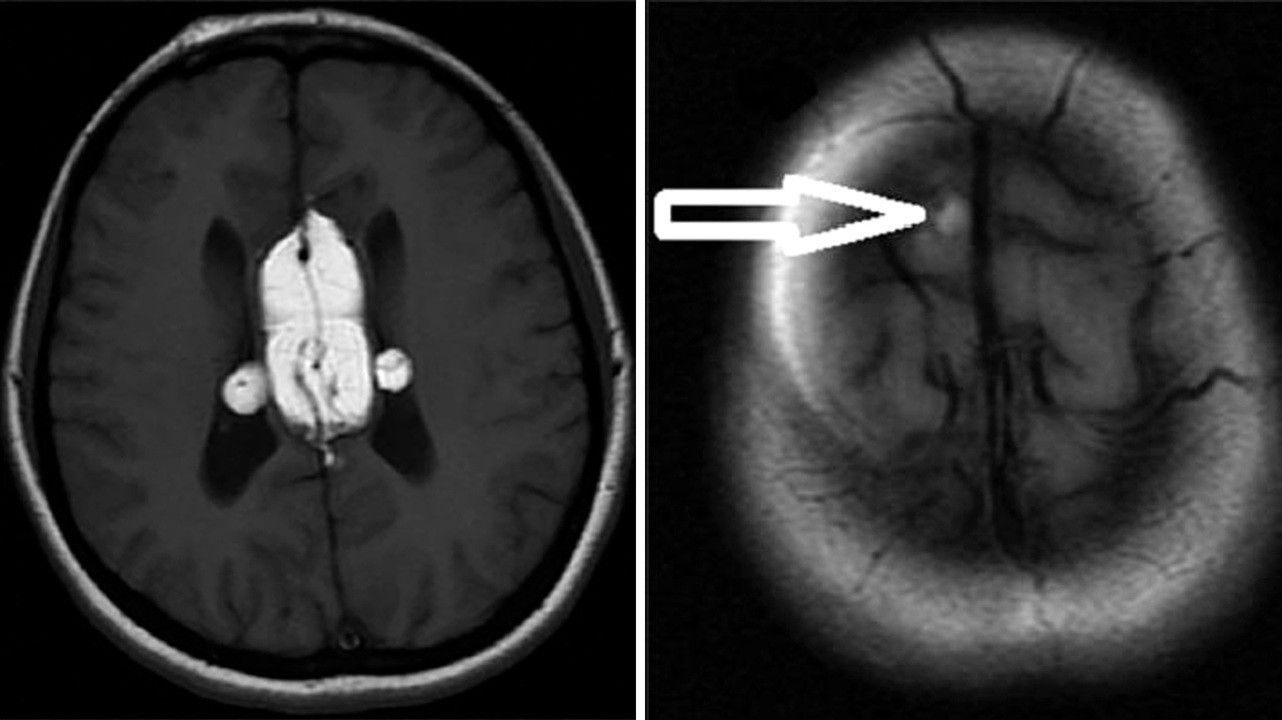

Липома головного и спинного мозга

Липомы головного мозга также выявляют случайно, когда у пациентов старшей возрастной группы проводят МРТ или КТ мозга по каким-то другим причинам, например, при нарушении когнитивных функций, эпилепсии. Липомы могут быть обнаружены в любом отделе мозга, тем не менее 50% – это перикалозальные липомы, в свою очередь 45% которых ассоциированы с агенезией мозолистого тела. 25% составляют липомы квадригименальной цистерны и 15% – липомы супраселлярной цистерны. Так как липомы мозга не имеют симптомов, хоть и часто сочетаются с какими-то пороками, например, агенезией мозолистого тела, то и лечения они не требуют. Хирургическое лечение сопряжено с большим риском осложнений и не имеет никаких преимуществ. Если возникают гидроцефалия или судорожный синдром, то лечение проводят по общим правилам.

Липома мозолистого тела головного мозга. Фото: Journal of neurosciences in rural practice / Open-i (Attribution-NonCommercial-ShareAlike 3.0 Unported)